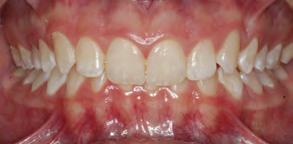

Paciente masculino de 23 años de edad el cual acudió al servicio de Odontología para valoración odon tológica anual como parte del exa men médico anual quien refiere a Cirugía Maxilofacial del Hospital Regional Naval de Acapulco (Figura 1). El paciente mencionó inicio de padecimiento con aumento de volu men y úlcera en paladar blando de 6 meses de evolución con salida de

material purulento (Figura 1). Negó crónico degenerativo, alérgicos y res to de antecedentes sin importancia. Se solicitaron estudios de laboratorio prequirúrgicos los cuales se encontra ron dentro de los parámetros norma les.

Paciente Figura 1. Fotografía clínica frontal. Figura 2. Con aumento de volumen y úlcera en paladar blando.